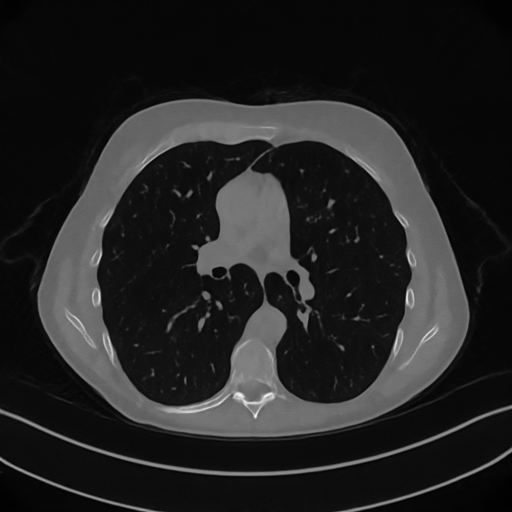

Here we present the results of RISING applied to the Mayo data set introduced in paragraph 4.1. As previously mentioned, we consider two sparse-view CT geometries, namely and . In Figure 4 we report the results for the protocol, achieved on one image of our test set. The top-left image represents the reconstruction. Even if only a small number of iterations are performed, the main structures of the abdomen are visible; however, the image is still blurry. In the image, shown in the upper-right corner, we notice that the TV regularizer has acted to totally eliminate the artifacts and noise, improving the uniformity of the image in the inner structures. When compared to the ground-truth solution in Figure 2, the contours of the details in appear slightly jagged, differently from where they are neat but, usually, corrupted by artifacts. The bottom row of Figure 4 shows the two and images, respectively from left to right. It is evident that has retrieved many details but it presents noisy components, reflecting the features of its target image . Our solution is less corrupted, since the low-contrast regions are correctly preserved and the noise is not visible. These observations are confirmed by Figure 5, which plots the intensity profiles taken over the red line in the second crop (Figure 2). In our approach (on the right) the CNN has accurately learnt the map of (8) and the red profile mostly overlaps the black one. On the contrary, the profile (on the left) is more distant from its target reference.

We now consider the CT protocol whose results are reported in Figure 6.

In this case, the tomographic reconstruction is more challenging than in the previous experiment. The starting image has evident streaking artifacts and blur and some details are lost, especially in the first zoom. The artifacts are reduced in the (top right image), where some details are recovered and the edges are quite neat.

The image obtained with the proposed RISING (bottom right) is visually an excellent reconstruction. It is very similar to the image, whose training, we remark, is based on more informative target images.